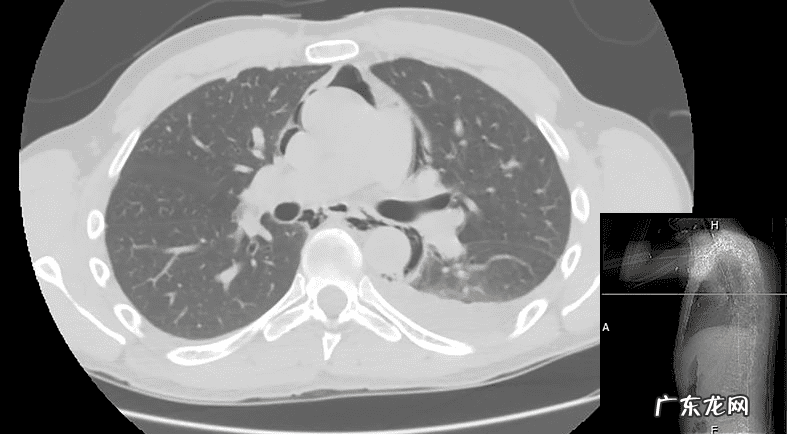

胸片检查发现左下肺有大片浸润影,纵膈气肿,没有明显的胸腔积液和气胸的迹象 。由于患者肾功能异常不能进行增强CT扫描,仅进行胸部CT平扫检查,结果提示,纵膈气肿累及双侧上胸腔和颈部,左肺下叶浸润及胸腔积液(图1) 。

图1 急诊胸部平扫影像